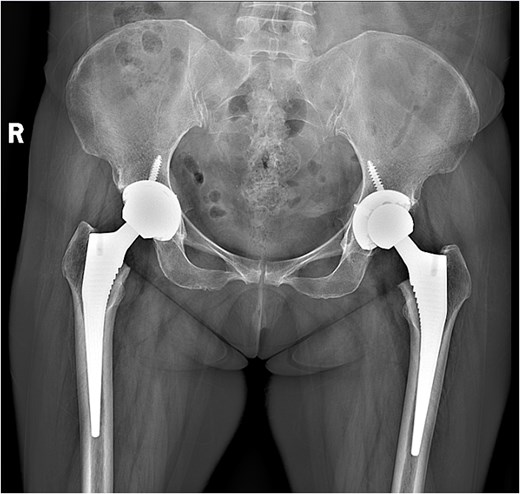

A 47-year-old woman, weighing 65 kg with a height of 158 cm and a body mass index (BMI) of 26 kg/m2, came to our hospital with chief complaints of bilateral hip pain and difficulty walking for 1 year and underwent left THA and 1 week of right THA because of bilateral avascular necrosis and collapse. X-ray of the pelvis of both hips revealed bilateral avascular necrosis and collapse (Fig. 1). A posterolateral approach was used for the bilateral hips in the lateral decubitus position. The implant consists of a Pinnacle cup (DePuy), DELTA ceramic liner and ceramic femoral head (BIOLOX DELTA), and collarless Corail stem (DePuy). After fixation of the acetabular cup, the senior surgeon placed the ceramic liner into the metal shell by hand. Unfortunately, the liner was not placed in the centre position and became stuck. The edge of the tilted ceramic is slightly greater than the cup, perhaps only 5 mm or less. The surgeon attempted to remove the liner by tamping the edge with the plastic impactor using light force several times, but the process of doing so fractured the ceramic liner (Fig. 2). The alumina ceramic fragment of the liner was removed carefully (Fig. 3), and the site was irrigated well. A 32-mm polyethylene liner and a ceramic femoral head were implanted. Full weight-bearing was allowed on postoperative day 1 with a walking aid. The patient remained hospitalized for 8 days to monitor closely for early perioperative complications. Sutures were removed on the seventh day, and the laboratory results indicated an absence of infection. At the 2-month postoperative interval, the patient achieved a successful outcome, with complete resolution of her preoperative symptoms as well as a return to all her activities of daily living (Fig. 4).

A radiograph was obtained preoperatively of a 47-year-old woman with bilateral avascular necrosis and collapse.